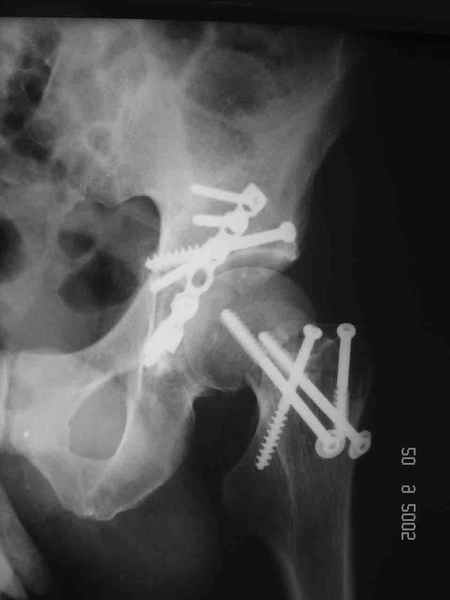

Привет! Вот недавно прооперировали похожий на ваш случай - впадина + шейка (правда у нас впадина поперечный+задний край). После травмы прошло 4 недели. мужчине 46 лет. С такой комбинацией все показания к первичному протезированию. Морально и технически мы к этому уже созрели.Но больной не собрал денег на протез. Выполнили остеосинтез впадины и шейки, прекрасно понимая, что головка вскоре рассосется, мы хотя бы надемся что к этому времени таз срастется, как говорится создали все условия для дальнейшего протезирования (может, и протез в последующем подешевле будет, в смысле, без укрепляющего кольца?). Привет Рункову!